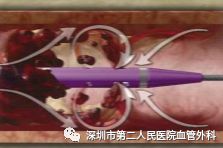

PMT是经皮机械血栓清除术,目前国内临床使用的主要是AngioJet Ultra 血栓清除系统,其原理是运用了流变学伯努利原理,能够有效清除血栓,迅速减轻血栓负荷,使症状快速获得缓解;快速开通血管,恢复血流,改善远端血供;减少平均住院时间,节省整体治疗费用。(图13-14)

图13 血栓被喷射水流击碎、被吸进导管并排出体外